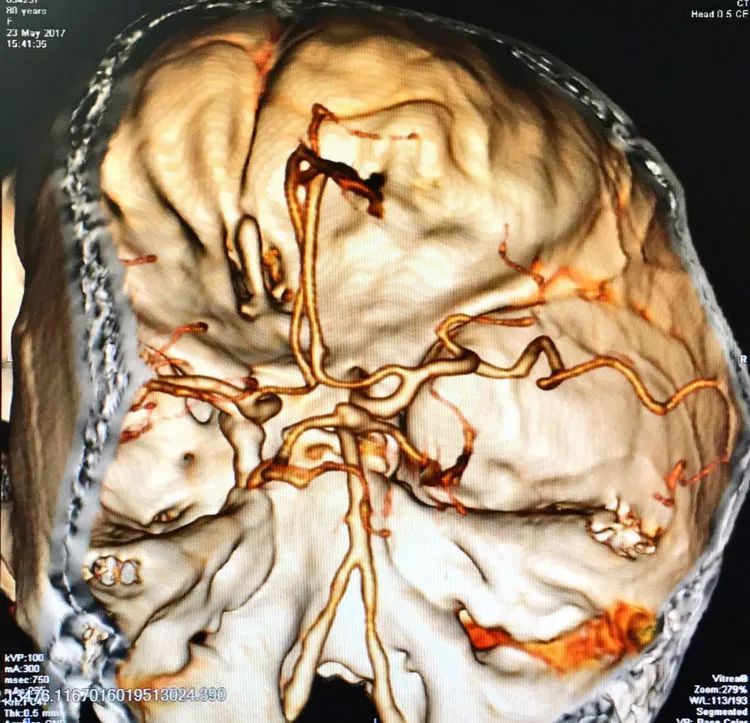

患者女性,80岁,以SAH于2017.5.20急诊入院,CTA示基底动脉顶端动脉瘤。

左椎动脉造影三维重建和测量